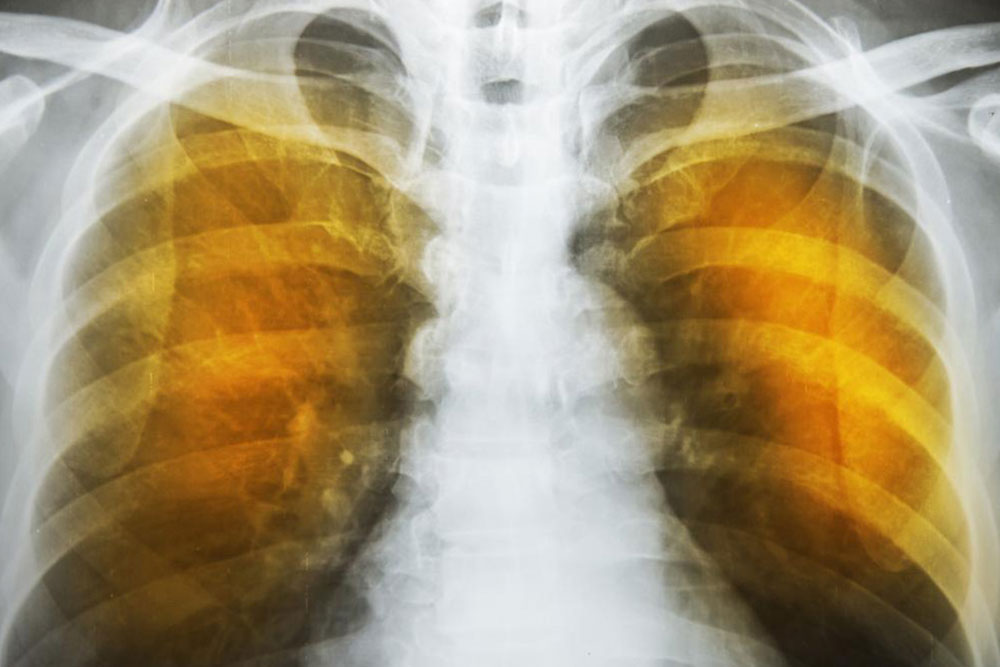

The next reaction is to cough out the irritants and the mucus. Severe forceful coughs can raise the pressure in the alveoli considerably and can rupture their exceedingly thin walls. The reduction of area for gas transfer and the loss of elastic tissues in the lungs reduces the capacity of the lungs to expel air. This reduces the intake volume of fresh air during breathing and can also lead to infections. These conditions produce the characteristic symptoms of wheezing, tightness in chest, labored breathing and coughing. These are also indications as well as symptoms of severe asthma.

As the deterioration continues, the alveoli lose their strength and start rupturing. In extreme cases, there may be large scale destruction which leads to empty spaces in lungs called bullae. This would reduce the functional area of the lung which in extreme cases call for surgical removal. In an extremely rare condition, large scale rupture of alveoli can cause a condition called pneumothorax and the collapse of the lung, a very serious condition, which can be fatal. The best thing one can do is stop exposure to irritants.